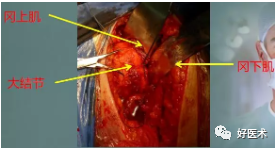

大结节--冈上肌、小圆肌--向上向后移位

-

小结节--肩胛下肌--内侧移位

(2)如何软硬兼施:

识别肱二头肌长头腱

识别分离的骨块和附着肌腱